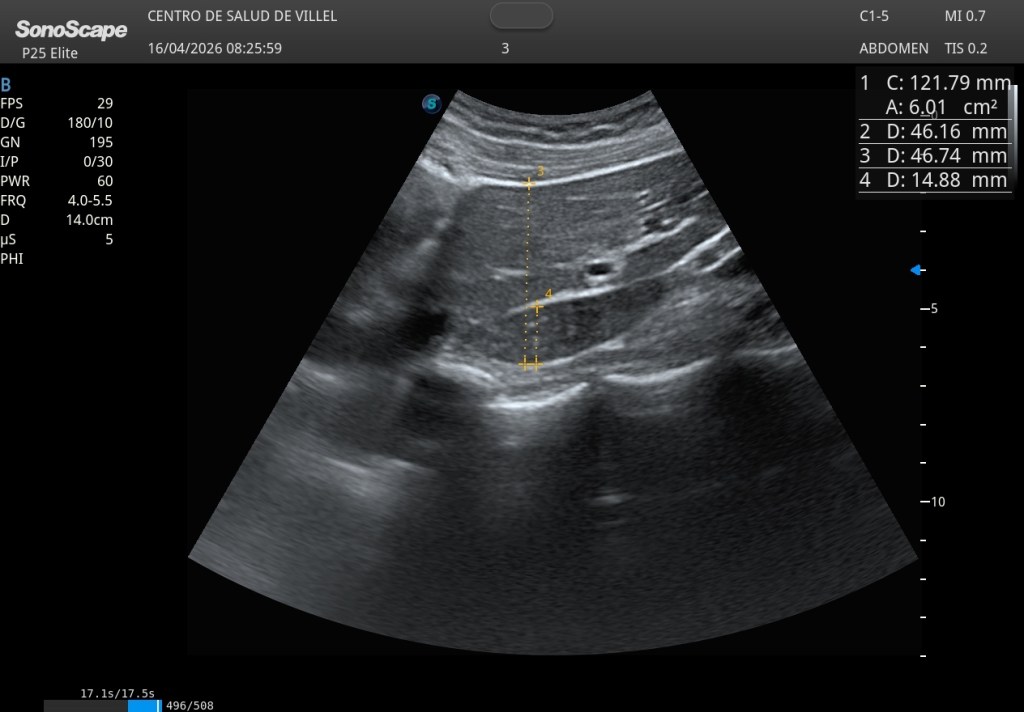

La técnica consiste en obtener un corte longitudinal parasagital que incluya el lóbulo izquierdo y el lóbulo caudado, y en ese plano medir dos diámetros anteroposteriores: por un lado el espesor del lóbulo caudado y, por otro, el espesor combinado del lóbulo izquierdo más el propio caudado. A partir de esta relación se establece una regla muy sencilla: si el diámetro del caudado supera un tercio del espesor total combinado, puede sugerir hipertrofia del lóbulo caudado.

Expresado de otro modo, si el lóbulo caudado representa más del 33 % del espesor total medido, debemos prestar atención. Pero quizá el aspecto más interesante desde el punto de vista práctico es el inverso: si el lóbulo caudado es inferior a un tercio de la medida total, podemos considerar orientativamente que no existe hipertrofia caudada significativa como la imagen que te muestro a continuación.

Este concepto convierte una sospecha compleja en una apreciación intuitiva. Casi visual. Un signo de cabecera que puede ayudarnos a objetivar algo que muchas veces valoramos solo por impresión. Ahora con medidas de normalidad: